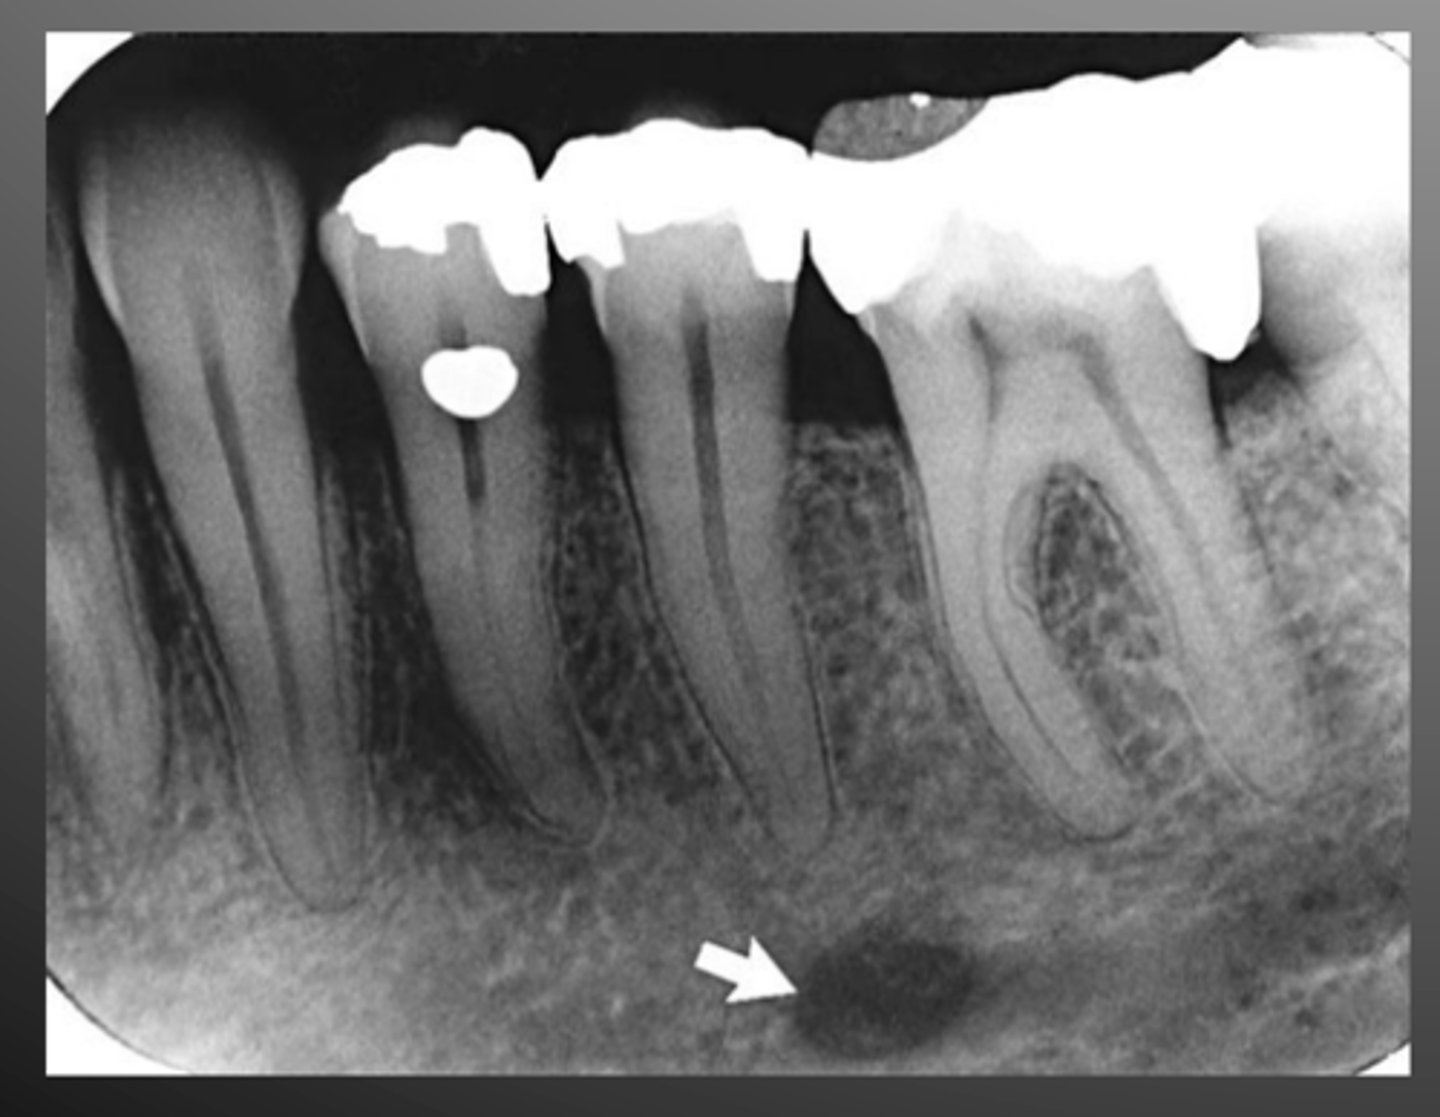

mental foramen

hole between roots of premolars

genial tubercles

bone spikes on the inner surface of the mandible

appear as a circle in images

lingual foramen

located within genial tubercles